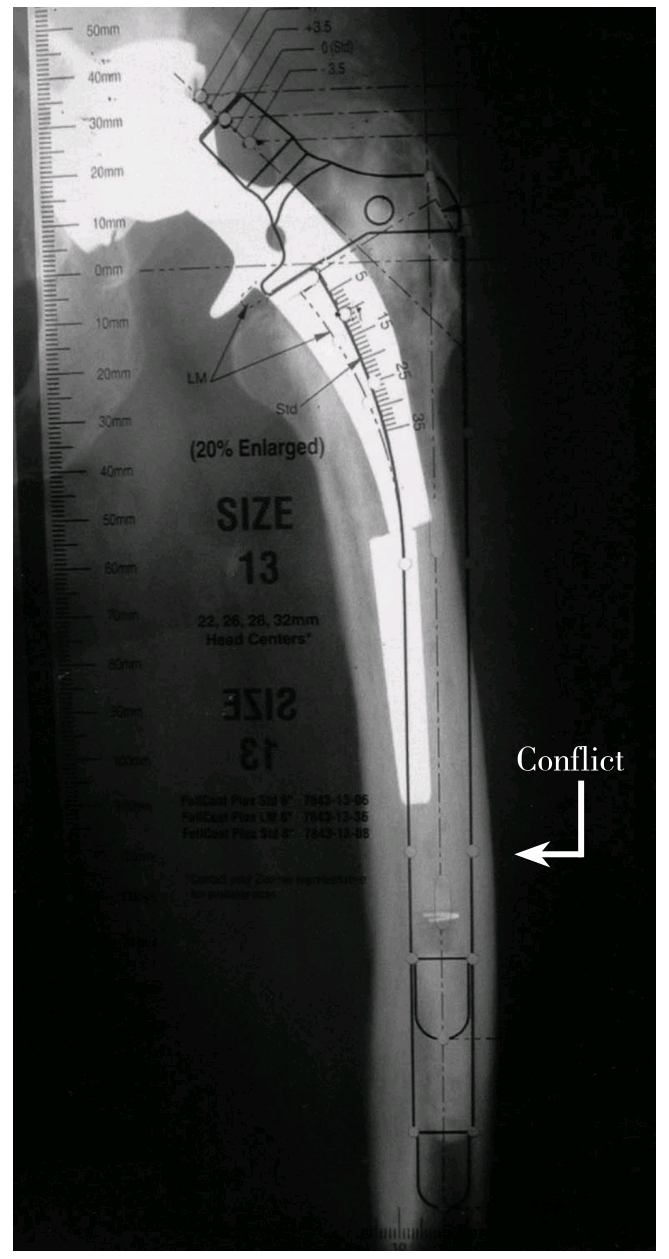

人工髋关节翻修术的模板测量步骤与初次置换相同,首先测量髋臼侧,标记确定旋转中心后,然后再围绕旋转中心进行股骨侧模板测量。模板测量时应注意以骨缺损分型为指导选择合适类型的假体,其大小可用模板在X线片上重叠测量。以髋臼侧翻修最常用的多孔涂层的半球形髋臼杯为例,第一步将模板放置到X线片上,使髋臼杯获得最大骨性覆盖,若宿主骨与臼杯接触50%~60%,根据具体骨缺损情况可以选用骨小梁金属臼杯、髋臼支架结合结构性植骨、Cup-Cage结构、定制三翼臼杯等(详见第四章)。股骨柄的长度一般应越过任何股骨缺损(bypass defects),并超过该处股骨髓腔直径2~3倍的长度。对于广泛涂层股骨柄而言,其宽度(直径)应能满足与远端完整皮质骨的接触区域大于5cm,以提供充分的初始稳定。若担心强度不够,应考虑准备异体骨板,术中支撑性植骨(strut graft)以增强股骨强度,降低骨缺损部位的骨折风险。若所选假体长度大于15cm时,必须在侧位片上评估假体与股骨前弓匹配程度,以确定是否用一个弯柄而避免造成股骨骨折或穿孔。此外还应注意所选假体应该有适宜的颈长及偏心距,以尽量纠正双下肢不等长及优化外展肌功能,防止碰撞。(旋转中心的确定应根据下肢计划延长多长,旋转中心则应相应垂直提高多少来定;偏心距应在内旋15°的正位片上来确定,以抵消股骨前倾)。

术前X线测量评估时一个重要而又易被忽略的部分是对股骨畸形的评估。松动的股骨假体常伴有股骨重塑(remodelling)致内翻和后倾畸形,而术前模板测量有助于辨识股骨重塑。图1-3-7所示:用模板测量时,植入假体柄的远端部分应放于股骨髓腔中央,柄的外侧边界与股骨外侧皮质之间的位置关系可以对比出来。如果假体接触或位于股骨外侧皮质之外,则提示发生了股骨内翻重塑,此时就应该决定在术中显露时做ETO,否则术中扩髓时将会有股骨穿孔的风险,若自髓腔植入假体尺寸不合适,还可能导致骨折。

术前模板测量有助于辨识股骨重塑